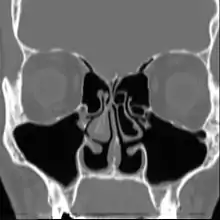

Le syndrome du nez vide (SNV), de l’anglais : Empty Nose Syndrome (ENS), est un état qui apparaît lorsqu'une quantité excessive de tissu nasal producteur de mucus (les cornets ou turbinates en anglais) a été chirurgicalement enlevée du nez ou endommagée, laissant un vide ou des dommages trop importants dans les cavités nasales. Une chirurgie conservatrice peut également mener au syndrome du nez vide car il n'y a pas de standard, ni études, sur la quantité du cornet qui peut être réséquée avant de développer le Syndrome du Nez Vide.

Lorsqu'une quantité excessive des cornets est ôtée ou endommagée, le nez perd ses capacités à convenablement pressuriser, diriger, tempérer, humidifier, filtrer, sentir et détecter le flux d'air inspiré. La synchronisation respiratoire naturelle entre le nez, la bouche et les poumons est également perturbée.